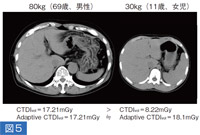

被写体が小児の場合、日常の検査中にパネルに表示されるDose Reportよりも、最大で2倍近く被ばくしていることがあることをわれわれは知っておくべきであろう(図5)。 |

図5

左は体重80kg、69歳、男性の上腹部単純X線撮影CTである。パネル上のCTDIIvolは17.21mGyを示していたとする。これに対し体重が約半分の30kg、11歳、女児の腹部CTで、仮に線量を半分に設定すると、パネル上はCTDIIvolは8.22mGyで、見かけ上は数値は半分になる。しかし、体格を加味した断面で計算するadaptive CTDIでは18.1mGyである。